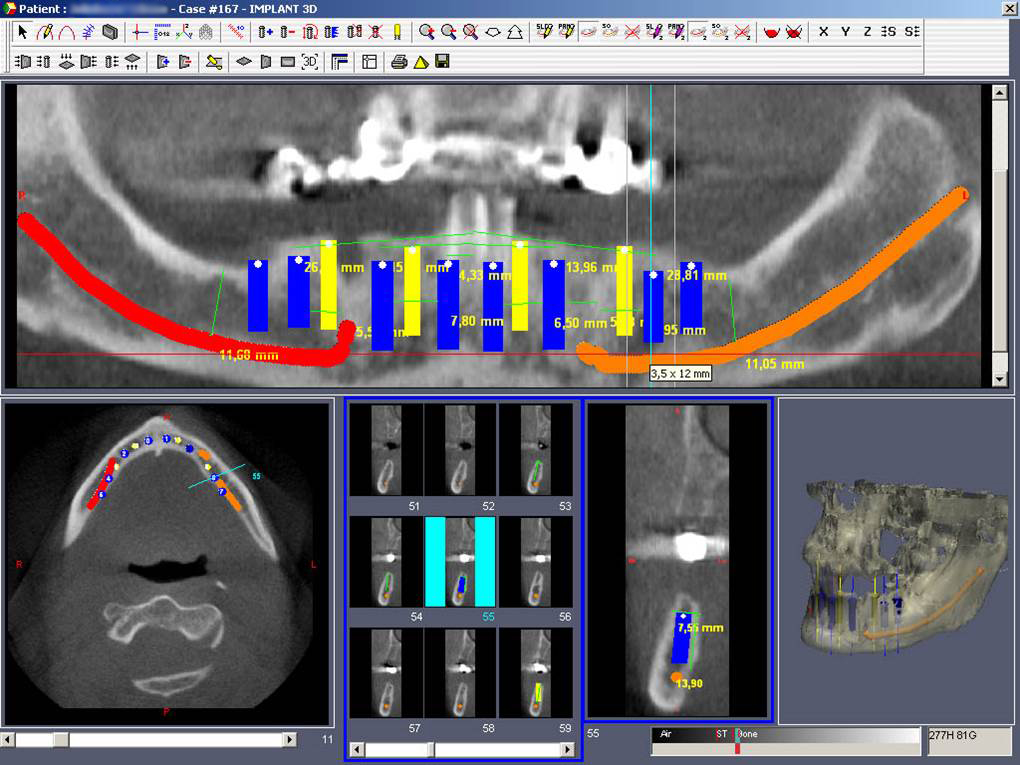

• Dokonalé vyšetření, stanovení diagnózy,naplánování ošetření - způsob, časový průběh,cena

Základní podmínkou pro ošetření pomocí implantátů je dostatečné množství zdravé, kvalitní kosti v čelistech. Dalším důležitým předpokladem je dokonalá ústní hygiena. Také celkový zdravotní stav pacienta hraje významnou roli. Některá systémová onemocnění, jako je diabetes, hypertenze, onemocnění žláz s vnitřní sekrecí, užívání některých skupin léků apod. mohou v některých případech ovlivnit úspěšnost implantace. Také nadměrné kouření či užívání alkoholu nebo jiných návykových látek mohou způsobit komplikace při ošetření pomocí implantátů. Vždy je nutné o těchto záležitostech informovat svého zubního lékaře!

Průměrná doba hojení implantátů před provedením definitivního protetického ošetření je 3-4 měsíce, v případech, kde je nutné doplnit chybějící kost (různé metody, postupy a materiály) – tzv. augmentace) se může doba hojení prodloužit na 8-12 měsíců. S tím je pacient vždy předem seznámen svým lékařem.